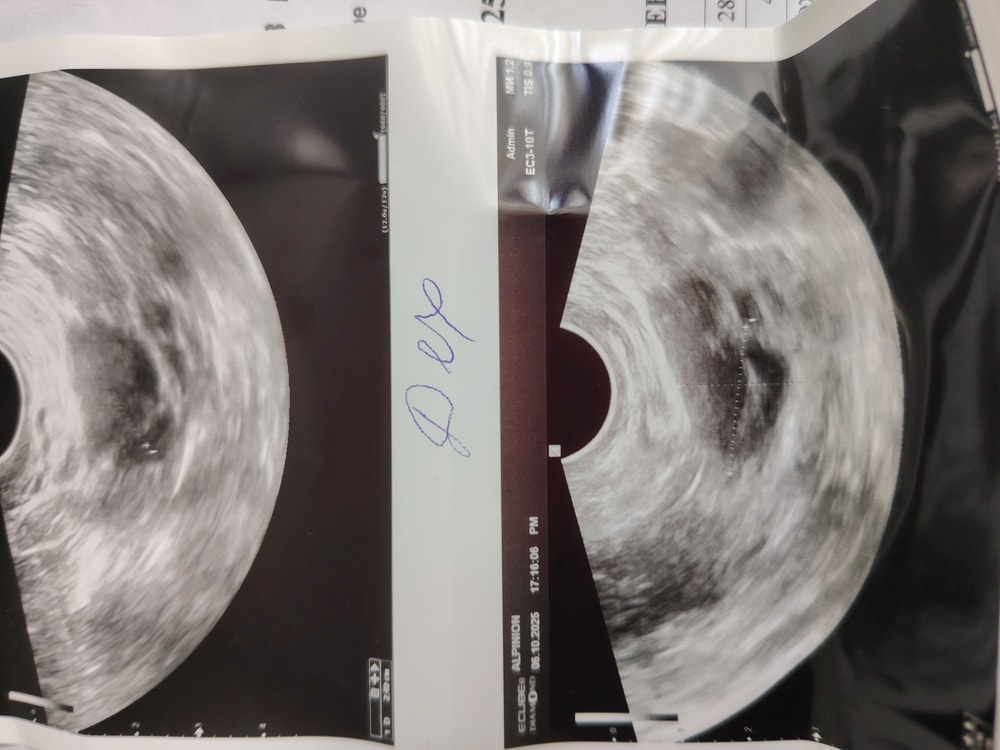

Мамаша в Зачатие 2 месяца Нормальный ли фолликул? УЗИ Нормальный ли фолликул? Он 25 мм. Не кривой? Знающие посмотрите. Может конечно я накручиваю себе. Был укол овитрель Посмотрите еще 20 записей на эту тему Отменить Ответить Когда на узи Хгч, выделения Чаты Беременных Выберите чат: Январята-2026 Февралята-2026 Мартята-2026 Апрелята-2026 Майчата-2026 Июнята-2026 Июлята-2026 Августята-2026